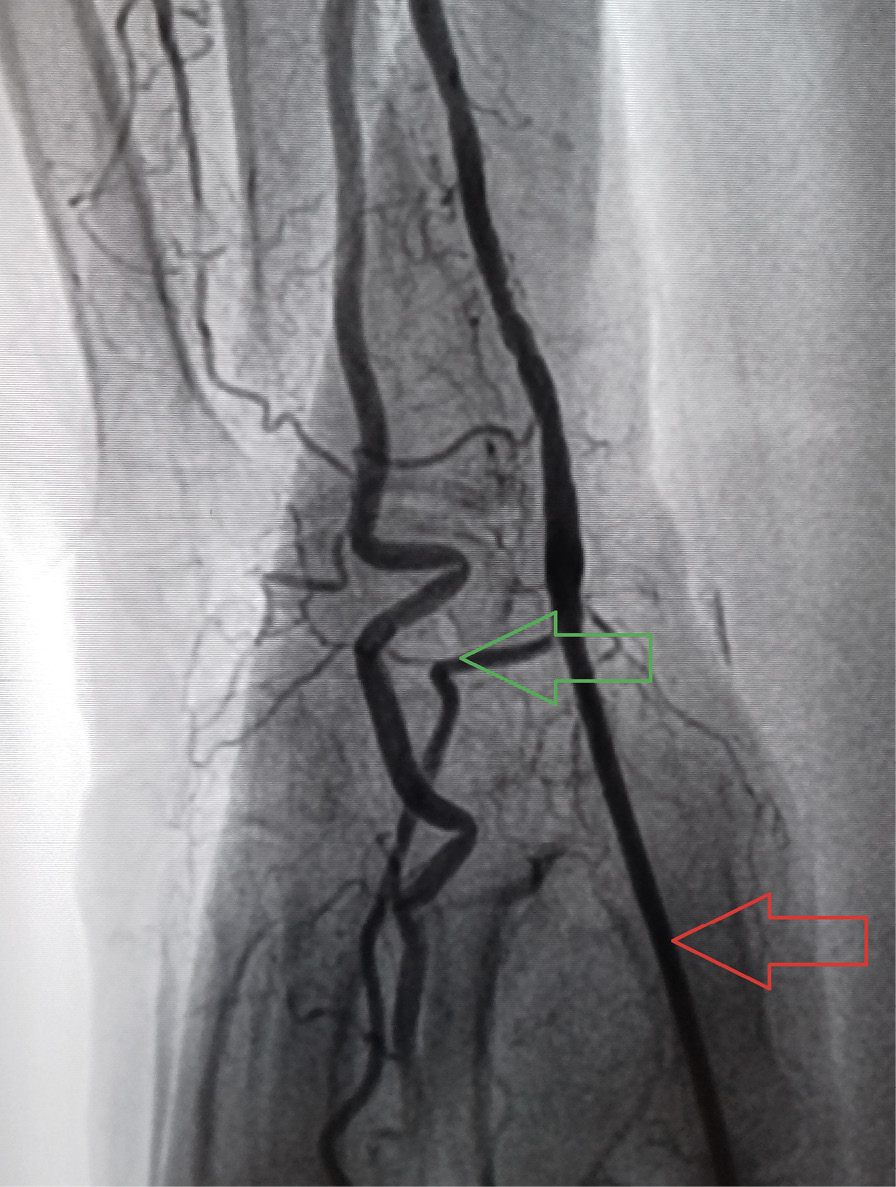

По данным осмотра, пальпации и УЗИ артерии доступа, проведенных на 5–7-е сутки после вмешательства, псевдоаневризма лучевой артерии отмечалась у 3 (3%) пациентов из группы ТРД, в группе ДпЛД данное осложнение выявлено не было. Случаев развития артериовенозных фистул в зоне доступа не отмечено ни в одной из групп. ОЛА предплечья выявлена у 3 (3%) пациентов группы ТРД. В группе ДпЛД случаев ОЛА предплечья выявлено не было. ОЛА дистальных отделов с сохранением кровотока в лучевой артерии предплечья («дистальная» ОЛА) отмечалась у 3 (3%) пациентов в группе ДпЛД (рис. 4). Кровоток в лучевой артерии предплечья при этом был сохранен. Случаев развития дистальной ОЛА у пациентов группы ТРД выявлено не было. Учитывая малый объем наблюдений, предикторы ОЛА, гематом и псевдоаневризм выявить не удалось. При этом все 3 (100%) случая ОЛА предплечья и 2 (66,6%) случая дистальной ОЛА были отмечены у пациентов женского пола. Следует отметить, что ни в одном из 6 случаев конверсии доступа (5 случаев ДпЛД и 1 ТРД) не было выявлено ОЛА предплечья и дистальных ОЛА «больших» гематом 3–5-й степени по шкале EASY, а также артериовенозных фистул. Помимо оценки состояния лучевой артерии у всех пациентов, включая пациентов с конверсией ТРД и ДпЛД, оценивали диаметр лучевой артерии на уровне предплечья и дорсальной поверхности ладони по данным УЗИ (табл. 4). Диаметр лучевой артерии на предплечье был значимо выше диаметра на дорсальной поверхности ладони у пациентов в обеих группах, независимо от типа выбранного доступа (2,75 ± 0,32 и 2,38 ± 0,36 мм в группе ТРД, p < 0,001; 2,84 ± 0,38 и 2,45 ± 0,36 мм в группе ДпЛД, p < 0,001). В то же время у пациентов с конверсией доступа диаметр лучевой артерии на обоих уровнях был ниже средних значений. Однако из-за малого количества наблюдений (1 пациент из группы ТРД и 5 пациентов из группы ДпЛД) статистически значимых различий выявить не удалось.

Рис. 4. Окклюзия дистальных отделов лучевой артерии по данным выполненного на 5-е сутки ультразвукового исследования артерии доступа (указана красной стрелкой), кровоток в поверхностной ладонной ветви лучевой артерии (указана зеленой стрелкой) сохранен [17]

У 3 (3%) пациентов в группе ДпЛД выявлена ОЛА в дистальных отделах с полным сохранением кровотока в лучевой артерии предплечья. По данным литературы, окклюзия дистальных отделов лучевой артерии возникает в 5,2% случаев, несмотря на меры по предотвращению травм эндотелия (УЗ-ассоциированная пункция, использование инструмента с диаметром 5Fr, а также внутривенное введение гепарина, спазмолитических коктейлей (нитроглицерин, верапамил)). Причины ОЛА дистальных отделов до сих пор остаются неясны. Дистальные отделы лучевой артерии, обеспечивая функционирование лучевой артерии предплечья в период гемостаза, становятся уязвимы для посткатетеризационной окклюзии [25]. Несмотря на преобладание конверсий среди пациентов группы ДпЛД (1 (1%) пациент из группы ТРД против 5 (5%) пациентов из группы ДпЛД), статистически значимого различия в частоте конверсий в нашем исследовании выявлено не было (р > 0,05). Причиной конверсии стал спазм лучевой артерии. Независимо от группы (ТРД или ДпЛД) нами не было отмечено ни одной конверсии на феморальный доступ благодаря успешному использованию проксимального отдела лучевой артерии ипсилатеральной верхней конечности у пациентов с конверсией доступа в группе ДпЛД и контралатеральной конечности в группе ТРД. Данный факт актуален для пациентов с ОКС, у которых трансфеморальный доступ ассоциирован с более высокими показателями смертности от геморрагических осложнений [3], обусловленной спецификой данной категории больных (двойная антиагрегантная терапия, антикоагулянтная терапия, пожилой возраст).